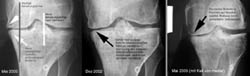

Die Schmerzen sind entweder immer noch da oder in letzter Zeit wenig stärker geworden - wenn sie auch im Alltag meistens nicht störend sind. Trotzdem: Es war wieder einmal eine Röntgenkontrolle bei Prof. Hans-Ulrich Stäubli im Salemspital Bern angesagt, der mich aus Chur übernommen hat - erfreulicherweise: Prof. Stäubli geniesst einen exzellenten Ruf (alle, die ich um ihre Meinung fragte, reagierten etwa so: "Ja, wenns DER sagt, dann ists auf jeden Fall so!") und hat u.a. auch schon andere Bündner Oberländer mit lädierten Knien operiert... hier bin ich also in besten Händen. Zudem liegt das Salemspital einen Steinwurf vor meiner Haustüre. Weniger erfreulich waren dann aber die Ergebnisse der Röntgenbilder: Das Knie muss so schnell wie möglich nochmals operiert werden. Das heisst wohl diesen Sommer nochmals den ganzen Karsumpel: Ops, Reha, Krücken, ... ich fass es nicht! Der Bericht ist hier abrufbar.

20. Mai 2005: Die Details sind bekannt

Anfang August solls so weit sein: Die Röntgenbilder zeigen, dass die Belastungsachse falsch liegt und die innere Gelenkfläche zu stark belastet ist. Hier gibts praktisch "Knochen auf Knochen". Durchgeführt wird nun eine "medial aufklappende, treppenförmige Tibia-Osteotomie", was soviel heisst wie: Schienbein unterhalb des Knies aufsägen, einen Keil rausnehmen und mit einer Platte wieder zusammenschrauben. Dies wird die Belastungsachse Richtung Mitte legen und das Gewicht besser verteilen. Dazu gibts eine Arthroskopie des Kniegelenks, bei der diverse Knochenwucherungen entfernt werden. Rund drei Monate Krücken sind angesagt. Im Vergleich zum künstlichen Kniegelenk, das mir in rund 20 Jahren blüht, Peanuts...

Montag, 19. September: Good News

Grauer Himmel, Bise, Kälte - doch die Röntgenkontrolle und Sprechstunde bei Prof. Stäubli verlief durchwegs positiv: Die Schrauben halten, die Stellung der Beine stimmt, die Gelenksachse stimmt. Nächste Kontrolle in drei Monaten - und in drei Wochen kann ich bereits die Krücken in die Ecke stellen. Das ist viel besser als erwartet.

Auch sonst ist fast alles in Butter: Schon seit zwei Wochen fühle ich, dass es möglich sein sollte, voll aufs operierte Bein zu stehen - erstaunlich für so einen komplexen Eingriff. Nun ists offiziell: Ab sofort kann ich daheim auch ohne Stöcke kurze Distanzen gehen. Medis nehme ich schon seit etwa zwei, drei Wochen keine mehr - auch das ist verglichen mit früheren Operationen erstaunlich. Strecken kann ich das Knie (zum ersten Mal seit dem Unfall im April 2001!) ganz, beugen bis etwa 110-120 Grad - in den letzten Wochen stieg dieser Wert fast täglich. Cool - alles durchwegs positiv also! Einzig ein kleiner Restschmerz im Osteotomiespalt ist noch vorhanden, dazu die üblichen kleinen Arthrose-Stiche im Knie. Bald gehts los mit deftiger Kräftigung, dann sollten die Muskeln auch schnell wieder zurück sein.

Paris, 17.12.2005 (Klicken für Vergrösserung)Lange Spaziergänge durch das weihnächtliche Paris erträgt mein Knie recht gut - mit den Schmerzen gehts in den letzten Tagen ganz sachte abwärts, immerhin. Auch velofahren geht wieder etwas besser. Aber bei besten Schneeverältnissen nicht auf der Piste zu sein mitten im Dezember - das bleibt schon gewöhnungsbedürftig. Auch die Röntgenkontrolle gestern im Salem brachte nicht viel Neues an den Tag: Mit dem Osteotomiespalt ist soweit alles OK, der ist schon fast kein Spalt mehr. Alles hält und heilt wie geplant. 20.12.2005: Das Öl ist da! (Klicken für Vergrösserung)Nur: Es wird weiterhin dringend vom Skifahren abgeraten. So werde ich die Weihnachtstage zum ersten Mal, seit ich denken kann, nicht skifahrend verbringen. Frust - besonders, weil heute Janica Kostelic mit ihrem lädierten Knie wieder mal einen Riesenslalom gewonnen hat. Ich versuche das ganze trotz allem Verdruss sportlich zu nehmen: Wieso nicht mal Schneeschuhwandern versuchen? Zudem hab ich endlich das in Seillans vor drei Wochen "gepflückte" Olivenöl in der Hand und kann damit während der Festtage feine Sachen kochen: Schmeckt vorzüglich - die Physiostunden auf dem Baum haben sich also gelohnt. Das aktuelle Röntgenbild ist hier abrufbar.